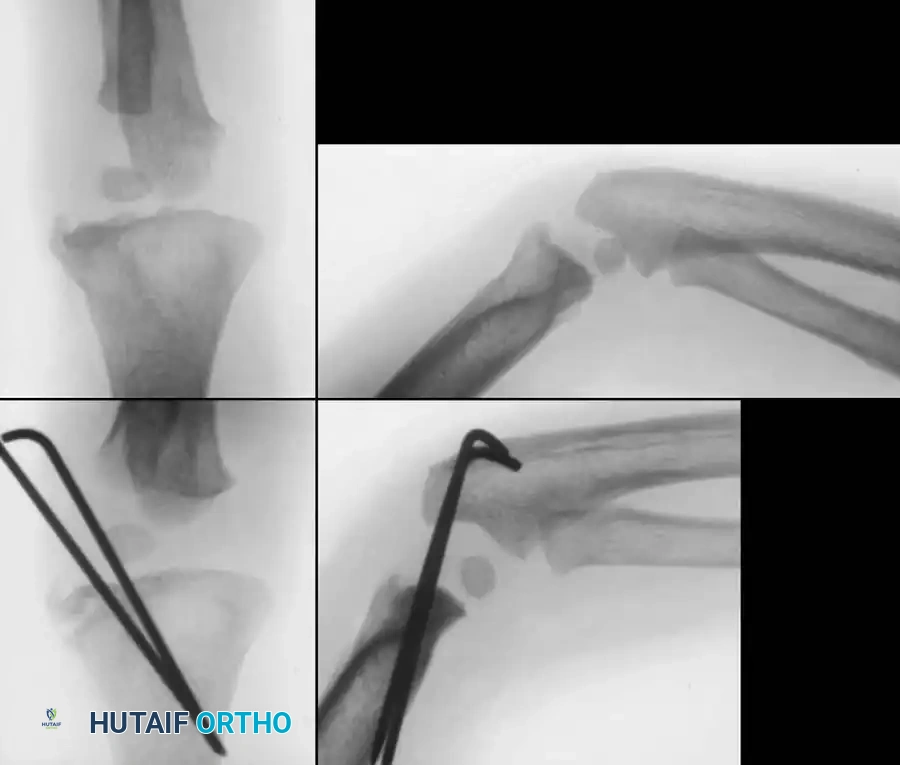

Fig. 33-44 A-D, Reduction of radial head by leverage method and retrograde intramedullary pinning with Kirschner wire.

Intraoperative Fluoroscopy and Pin Placement